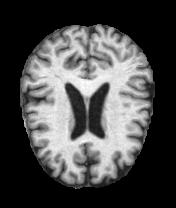

MRI Brain Scans Dataset - All Categories

Mild Dementia

Moderate atrophy

Real MRI scans showing progressive structural brain changes across all dementia stages

- • Total Images: 6,400+ brain scans

- • Normal Cognition: 3,200 cases

- • Very Mild Dementia: 2,240 cases

- • Mild Dementia: 896 cases

- • Moderate Dementia: 64 cases